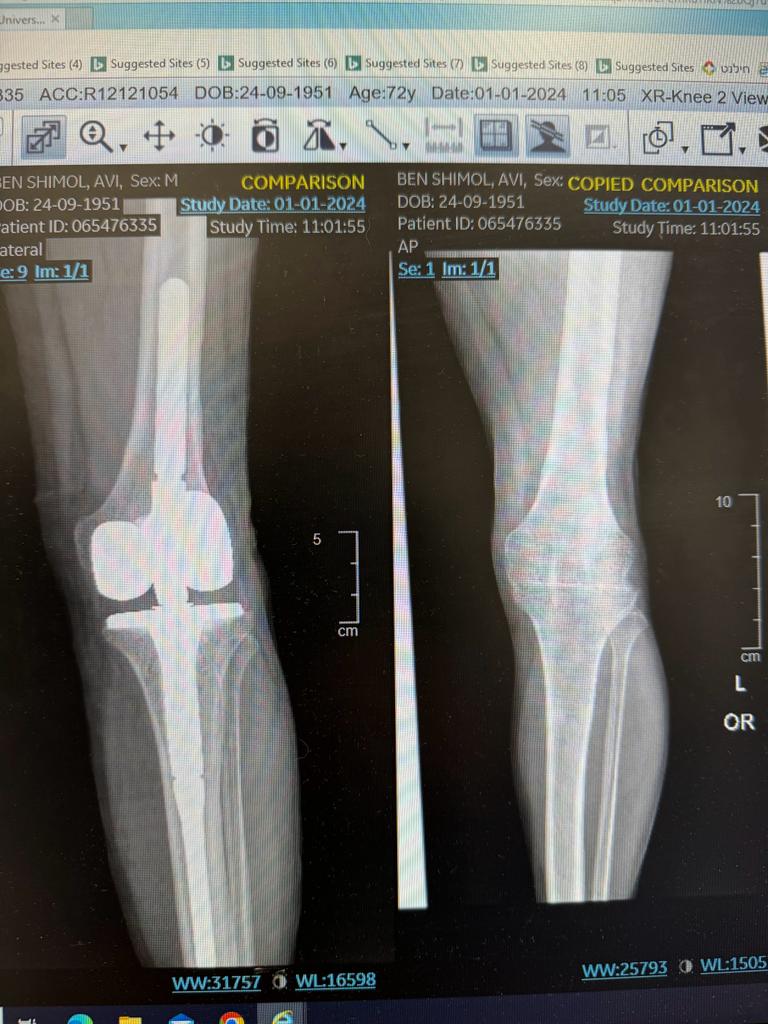

לאחר סדרה של הכנות לרבות צילומי רנטגן ו-CT, החליט פרופ' דרקסלר לבצע במטופל ניתוח פורץ דרך של בניית מפרק חדש לחלוטין באמצעות משתל מיוחד, ולהשתילו בגופו של מר בן שימול.

הניתוח נעשה לפני שבועות בביה"ח ולקחו בו חלק רופאים ממחלקות אורטופדיה כלי דם והדמיה.

לשמחת כולם הניתוח עבר בהצלחה וכבר למחרת, 36 שנים לאחר שלא יכול לעשות כן, המטופל הצליח לכופף את רגלו ולחזור לבצע פעולות יומיומיות בסיסיות כמו ישיבה.